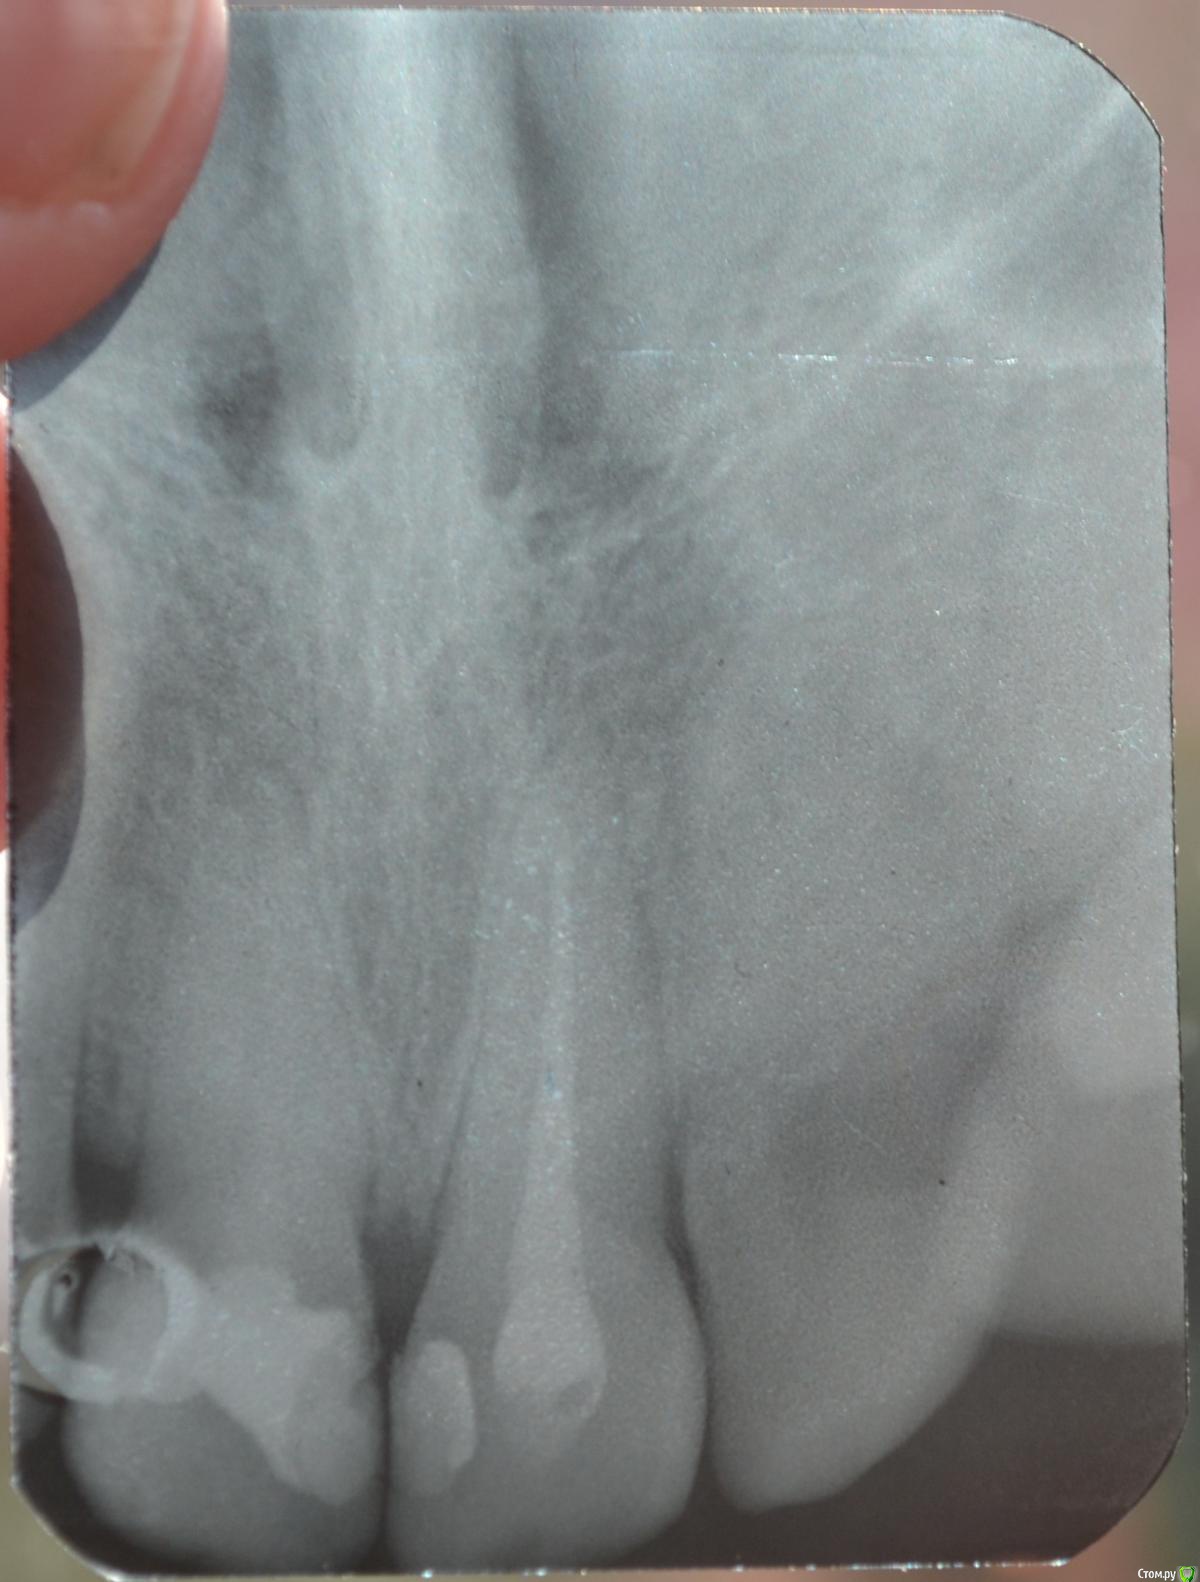

Llllll Опубликовано 11 июля, 2015 Автор Поделиться Опубликовано 11 июля, 2015 1 справа верхний, до того как открыли недавно каналы. Ссылка на комментарий

Llllll Опубликовано 12 июля, 2015 Автор Поделиться Опубликовано 12 июля, 2015 Лучше бы прицельный снимок проблемного зуба(на ОПТГ ничего не видно).Это 2 снимка этого зуба, несколько раз сфотографировала, чтоб лучше было видно. Ссылка на комментарий

Llllll Опубликовано 12 июля, 2015 Автор Поделиться Опубликовано 12 июля, 2015 И есть ли воспаление корня на снимке? (правого или левого). Вообще врач думал во вторник удалять передний зуб, который болит. К другому врачу не могу пойти, так как город маленький, и врачей всего несколько. Это уже третий врач у которого была, и никто не знает что с зубом делать, и вообще от него ли это( Ссылка на комментарий

Llllll Опубликовано 16 июля, 2015 Автор Поделиться Опубликовано 16 июля, 2015 Сегодня делали рентген еще раз, и увидели на 1 зубе справа (тот, который болит) на самой верхушке корня кусочек инструмента. Рентгена нету, так как его на компьютере только смотрели. Сказали что достать его нельзя. Что делать? Ссылка на комментарий

Llllll Опубликовано 27 июля, 2015 Автор Поделиться Опубликовано 27 июля, 2015 Вот еще делали рентген с иголкой в зубе. Ссылка на комментарий